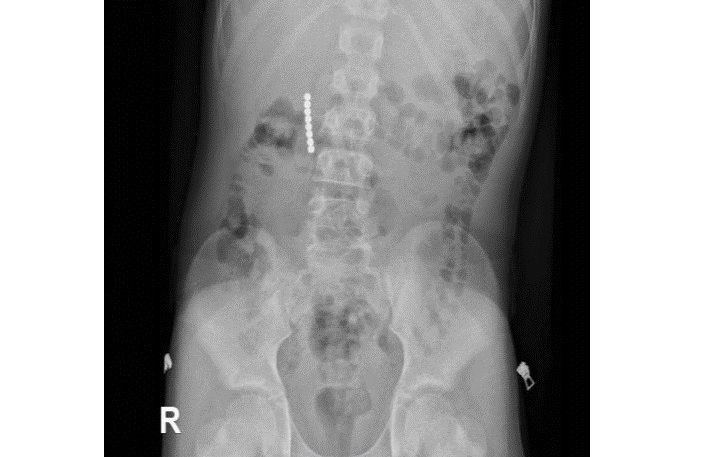

צילום: המרכז הרפואי בני ציון

מנהלת מחלקת ילדים במרכז הרפואי בני ציון ד"ר לילי היערי: "במהלך הניתוח, שבוצע בהרדמה כללית ע"י צוות המרדימים , צוות רופאי המחלקה בכירורגית ילדים בהובלת ד"ר דניאל דובין המרכז את תחום הכירורגיה זעיר פולשנית (לפרוסקופית) בכירורגית ילדים, בגישה לפרוסקופית, בשיתוף עם גסטרואנטרולוגית ילדים ד"ר נרמין שחאדה, הוצאו ממערכת העיכול של הילד שמונה כדורי מגנט קטנים. הניתוח עבר בהצלחה, הילד שוחרר לביתו בריא".